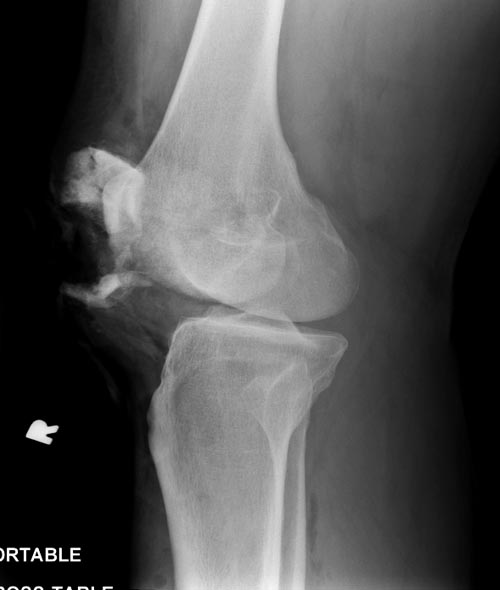

Здесь представлен посттравматический дефект латерального мыщелка и

лечение аллографтом.

Имя     : Medial Tibial plateau 1.jpg

Тип     : image/jpeg

Размер  : 34263 байтов

Описание: отсутствует

Url     : http://weborto.net:8080/pipermail/ortho/attachments/20141113/94e46382/attachment-0004.jpg